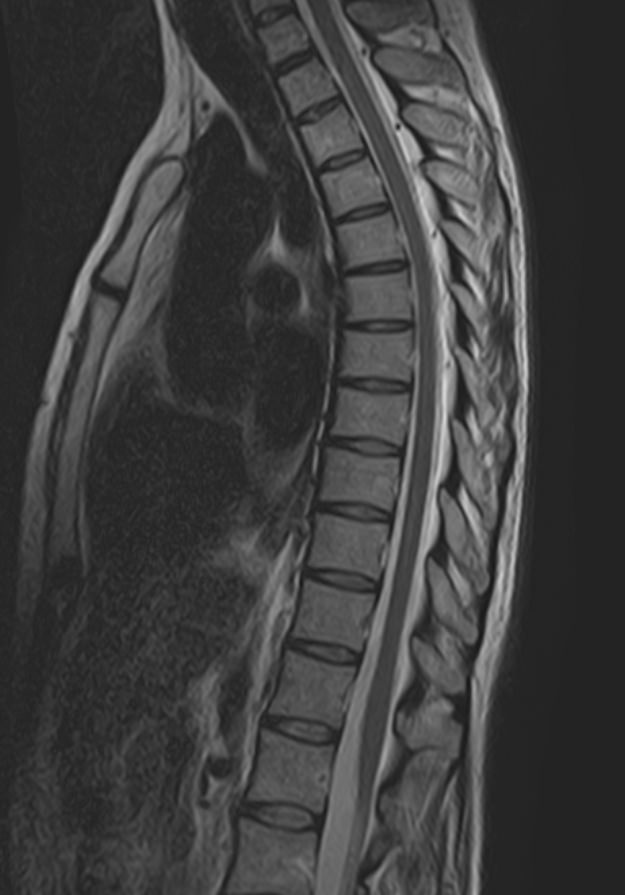

МРТ является современным высокоточным исследованием грудного отдела позвоночника, с помощью которого можно диагностировать различные заболевания, в том числе воспалительные, дегенеративные и опухолевые процессы. Преимуществом данного метода является его безопасность (отсутствие рентгеновского излучения), безболезненность, неинвазивность, при этом высокая информативность.

Клиника «Доступная медицина» оснащена новейшим томографом экспертного класса TOSHIBA VANTAGE TITAN 1,5 Тесла, который позволяет получать превосходные изображения с мельчайшей детализацией всех структур исследуемой области. Это позволяет ставить точный диагноз и выявлять различные заболевания позвоночника на самой ранней стадии.

С помощью МРТ грудного отдела выявляют следующие заболевания позвоночника:

• новообразования;

• степень повреждения спинного мозга в случае переломов тел позвонков;

• грыжи Шморля;

• травматические повреждения тел позвонков и остистых отростков (трещины, переломы, смещения и пр.) — при недоступности КТ;

• разрывы, растяжения связок;

• травмы спинного мозга, нервных корешков;

• протрузии;

• грыжи межпозвонковых дисков;

• остеохондроз позвоночника;

• стеноз спинномозгового канала;

• сосудистые патологии;

• остеомиелит, спондилодисцит;

• рассеянный склероз;

• спондилоартроз;

• спондилез.